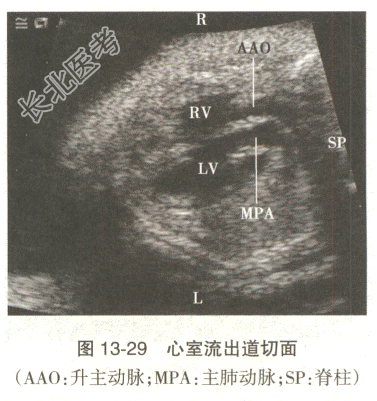

- [材料题] 患者,女性,35岁。孕2产1,孕25周,实验室检查及病史无明显特殊,心脏超声见图13-28、图13-29。

- 多项选择题1.根据上述声像改变,较合适的诊断包括

A、完全性心内膜垫缺损

B、右室双出口

C、法洛四联症

D、矫正型大动脉转位

E、完全型大动脉转位

F、左室双出口

- 多项选择题2.对于该胎儿心脏血流动力学,叙述准确的是

A、收缩期右心室血液射入主动脉内,左心室血液射入肺动脉内

B、舒张期左心房血液进入左心室内,右心房血液进入左心室内,收缩期右心室血液射入肺动脉内,左心室血液射入主动脉内

C、舒张期右心房血液进入左心室内,左心房血液进入右心室内

D、舒张期左心房血液进入左心室内,右心房血液进入右心室内

E、收缩期右心室血液射入肺动脉内,左心室血液射入主动脉内

F、舒张期右心室血液射入主动脉内,左心室血液射入肺动脉内